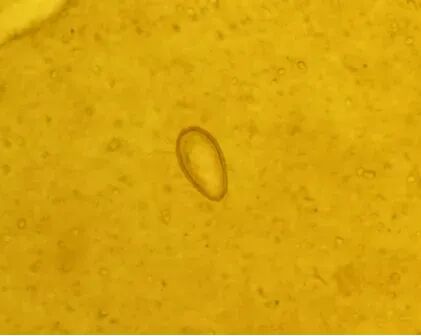

肝吸虫病学名华支睾吸虫病,是由华支睾吸虫寄生正在人体肝胆管内激发的食源性寄生虫病,次要因生食或半生食含肝吸虫囊蚴的淡水鱼虾传染,是典型的“病从口入”疾病。持久频频传染会激发胆囊炎、胆管炎、胆结石,严沉时导致肝软化,以至诱发胆管癌(世界卫生组织将其列为I类致癌物)。有必然风险。因为既往我省居平易近大多不生食淡水鱼,因而人群传染率极低,发觉的病例绝大大都是由高风行区输入的病例。但跟着饮食体例的多样化,当地居平易近已呈现生食淡水鱼的消费行为,人群传染肝吸虫风险升高。有生食淡水鱼虾史,且呈现发烧、腹痛、乏力、嗜酸性粒细胞增高档症状,及时到病院或疾控部分就诊,并自动奉告食鱼生史。确诊后应遵医嘱规范医治,切勿自行用药。